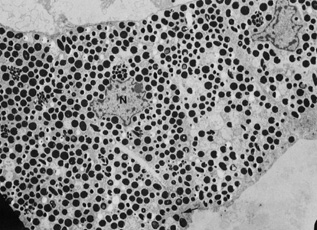

This layer is more heavily pigmented than its anterior counterpart. The cells are generally rectangular or pyramidal and contain large pigment granules. Scanning electron microscopic examination shows longitudinal furrows and pitlike structures (Fig. 20). Close inspection shows numerous pigment granules in the posterior pigment epithelium (Fig. 21). A thin basement membrane is present on the posterior surface of these cells. Numerous infoldings of the basal cell membrane are seen by ultratsructural examination. The lateral walls of these cells are joined to adjacent cells by maculae adherens and occludens. The cell nucleus is round, and the cytoplasm contains pigment granules measuring about 0.8 microns in diameter (Fig. 22). These granules are much larger than those found in the iris stroma, which range in diameter from 0.106 to 0.587 microns. The posterior pigment epithelium also contains glycogen, mitochondria, rough endoplasmic reticulum, and a Golgi apparatus.

Fig. 20. The posterior surface of the iris contains longitudinal furrows (arrow) and pitlike structures (scanning electron microscopy, ×54).

Fig. 21. Close inspection of the posterior surface of the iris shows numerous posterior pigment epithelial cells with prominent pigment granules (scanning electron microscopy, ×1000).

Fig. 22. The posterior pigment epithelium contains central-to-basal nuclei (N) and round, intracytoplasmic pigment granules that measure approximately 0.8 μm in diameter. Intercellular junctions (arrow) are present (×4750).